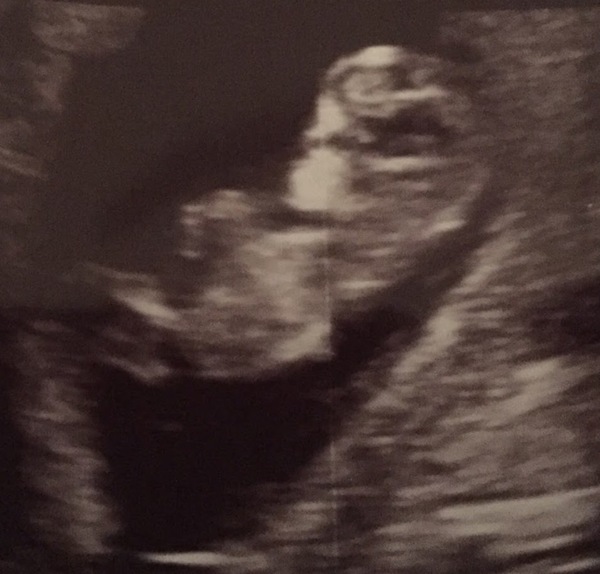

I've got a blob! Thanks everyone for your kind thoughts, I can't believe I've got a blob!!!

#TTC1 - Second Wave grads thread!

Whooop!!! And what a fine looking blob it is!!

Thanks you guys!! I'm 7+1, but some of the angles indicated it could be as early as 6+5 so somewhere in between those. I'm going with 6+5 and hoping I'll be put forwards at the 12 wk scan. It feels more real, and my DH is really happy and even talking about names etc! Obviously don't want to get too ahead of ourselves but this is a massive relief.

Yay, so pleased for you Skip! Lovely little bean you have in there!

There was a baby in there! Grin heartbeat 171 beats per minute, it was just about dancing a jig and I'm apparently further along than I thought at 10+4 according to measurements- or I'm just having a humongous baby ... it even had hiccups at one point!

Relief is immense. Both DH and I were in tears :-) the moment I first saw it move ... just OMG. We went to the Fetal Medicine Centre Moose and it was such a positive experience. We don't want to find out the sex though. Went to celebrate at a fondue restaurant afterwards- so so yummy!

That's amazing kav! Baby looks really developed! Could those dates work with your cycle do you think? Otherwise yay to big, happy baby! Haha